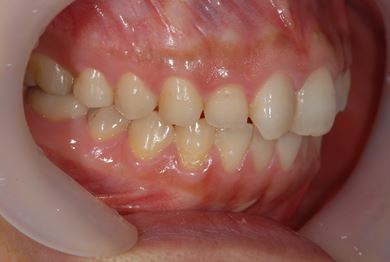

インプラント治療+セラミック治療+歯肉歯槽骨整形

| 性別/年齢 | 女性 / 38歳 | ||||||||||||||||||||||||||||||||

| 主訴 | 右下奥の欠損のため、インプラントを希望。また、左に物が挟まりやすいための治療も希望。 | ||||||||||||||||||||||||||||||||

| 治療内容 | インプラント1本、ジルコニアフレームオールセラミッククラウン2本(ジルコニアセラミック用土台1本)、歯肉歯槽骨整形 | ||||||||||||||||||||||||||||||||

| 総治療費 | 713,580円 | ||||||||||||||||||||||||||||||||

| 治療期間 | 10ヶ月 |